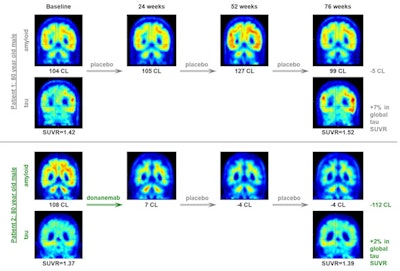

The primary focus of the phase II trial was the use of the "Centiloid (CL) scale," a method developed to standardize the results of amyloid PET scans in measurable units, with a score of 100 indicating "typical" Alzheimer's disease. In the trial, patients were considered to be completely clear with an amyloid plaque level of 24.1 CL, and some patients reached less than 11 CL by 24 weeks, the authors wrote.

In the present study, the group developed an exposure-response model that incorporated all available longitudinal pharmacokinetic and PET data from participants in the trial. According to the model projections, patients who achieved an amyloid load of 11 CL or less at week 24 and then discontinued amyloid treatment, the median time to reaccumulate amyloid from 11 CL to the 24.1 CL threshold could be 3.9 years, the authors wrote.

In addition, analysis of flortaucipir F-18 PET scans acquired of responding patients after 72 weeks showed a statistically significant 34% slowing of overall tau levels compared to placebo, according to the findings.